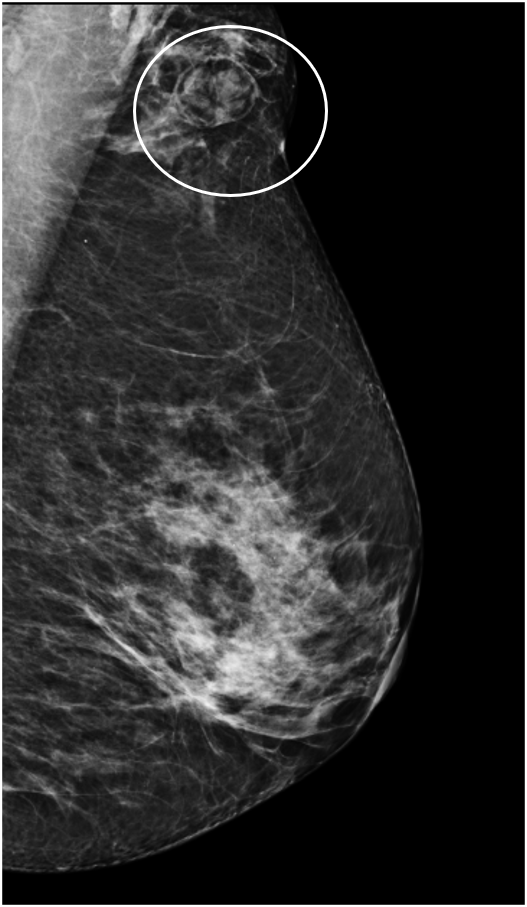

May 2023

44 yrs old Female Palpable lump in left breast for few weeks No right ...

Read More